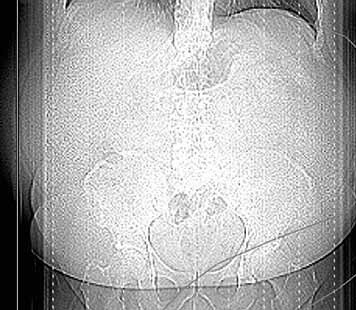

Die Klinik verfügt über 14 Computertomographen (CT), zwölf Magnetresonanztomographen (MRT) sowie zahlreiche Ultraschallgeräte. Allein am Campus Benjamin Franklin führen die Radiologen an sieben Tagen die Woche je zwischen 50 und 60 CT Untersuchungen täglich durch. Seit knapp drei Monaten steht ihnen dazu der neue 160-Schicht-Low-Dose-CT Aquilion PRIME zur Verfügung. Ein weiterer Aquilion PRIME sowie ein 640-Schicht-Volumen-CT Aquilion ONE ViSION EDITION wurden am Campus Mitte installiert. „Als wir nach einem neuen CT gesucht haben, war klar, dass dessen Ausstattung allen universitären diagnostischen Anforderungen gerecht werden muss", erklärt Dr. Stefan Niehues, Radiologe und Oberarzt der Klinik für Radiologie am Campus Benjamin Franklin.

„Mit dem neuen CT Aquilion PRIME können wir das komplette radiologische Spektrum der Charité abdecken. „Die gesamte Polytrauma-Diagnostik über die Akutversorgung bis hin zur Neuroradiologie und Diagnostik bei jungen Menschen führen wir mit dem Aquilion PRIME durch."

Neben der Rechnergeschwindigkeit lautet das Schlüsselwort bei dem neuen Gerät „Adaptive Iterative Dosis-Reduktion (AIDR 3D)". „Dieser mathematische Algorithmus erlaubt es uns, mit einem Bruchteil der Dosis zu arbeiten, die wir bisher für die erforderliche Bildqualität benötigt haben", weiß der Radiologe.

„Durch die Spitzentechnologie können wir bei gleich hoher Bildqualität die Dosis an Röntgenstrahlung bei vielen Untersuchungen auf ein Drittel reduzieren."